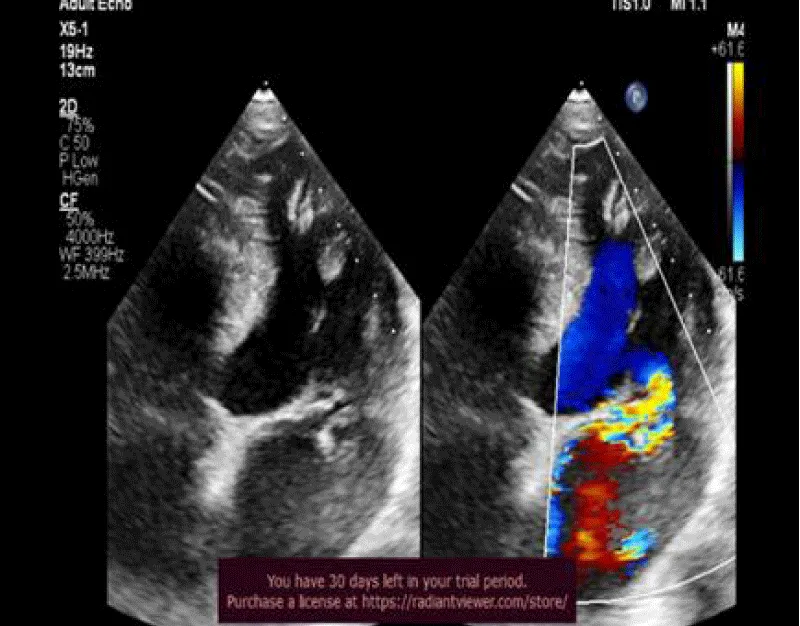

62 years old male, not known to be diabetic or hypertensive or a smoker presented with dyspnea on minimal exertion (NYHA class III). 2D echocardiography revealed flail posterior mitral leaflet with severe mitral regurgitation resulting in mild dilatation of LV, mildly impaired systolic function, EF = 56% and mildly impaired GLS = -17.2%. 3D echo revealed the same data with EF = 55%, GLS = -19.4%. CMR showed mildly dilated LV with mildly impaired LV systolic function, EF = 57%, GLS = -17.7%. No fibrosis was detected at LGE (Figures 1-5).

Figure 1: 2DTTE, 4 chamber view revealed myxomatous mitral valve disease with flail posterior mitral leaflet with severe MR, eccentric jet.

Figure 2: 2D speckle tracking of left ventricle revealed mildly impaired GLS = -17.2%.

25 years old male, presented by palpation. 2D echocardiography revealed MAD with mitral valve prolapse causing moderate to severe mitral regurgitation. Average LV volumes were noted with preserved systolic function, EF = 62 % and GLS = -19.7%. 3D echo revealed average LV volumes with mildly impaired, EF = 52% and mildly impaired GLS = -17.2%. CMR showed average LV with preserved LV systolic function, EF = 64% and impaired GLS = -13.1%. Nonterritorial subendocardial fibrosis was noted affecting the mid-segment of inferolateral and anterolateral walls (Figures 6-11).

Figure 6: 2D TTE revealed bi-leaflet MVP causing moderate to severe MR.

Figure 7: 2D TTE revealed MAD(systolic displacement distance =4.1 mm ,arrow).